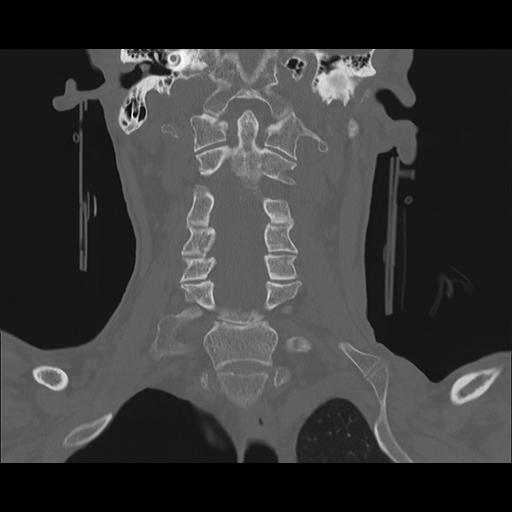

16 HUESO,,Coronal,2.000,HUESO,Coronal,